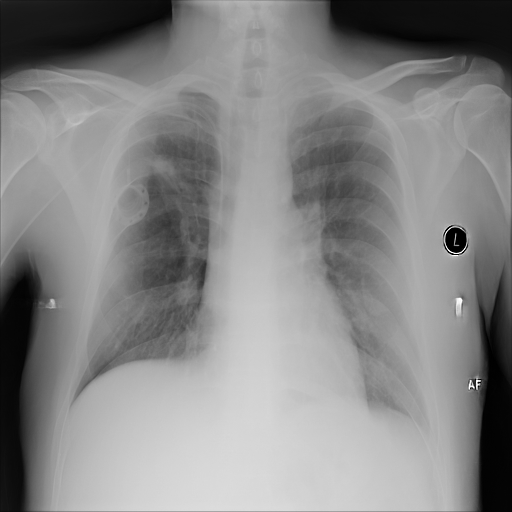

Refer to caption

(a) Original,

case 1 with a block.

(b) ϵ=102HWitalic-ϵsuperscript102𝐻𝑊\epsilon=10^{2}\cdot H\cdot W,

case 1.

(c) Original,

case 2 with a block.

(d) ϵ=102HWitalic-ϵsuperscript102𝐻𝑊\epsilon=10^{2}\cdot H\cdot W,

case 2.

Figure 4: Block obfuscation with DP-GLOW.

7.2 Qualitative assessment of LDP-processed CXR images

Here, we assume two possible privacy leakage scenarios. To CXR images, we intentionally add features that can lead to the re-identification of the subject appearing in a CXR image. The first feature is an artificial block marker. The second feature is a rare anatomical abnormality known as situs inversus simulated by flipping a CXR image along the vertical axis. Figs. 3(a) and 3(c) show CXR images with the artificial block marker. Fig. 5(a) shows a flipped CXR image to represent a case of situs inversus. We applied DP-GLOW to these CXR images. In Figs. 3(b) and 3(d), the image domain LDP fails to obfuscate the artificial block marker with a moderate privacy budget. In contrast, in Figs. 4(b) and 4(d), DP-GLOW successfully obfuscated the artificial block marker with the moderate privacy budget. On the other hand, the anatomical shape of the chest and the abnormal opacity (hilar regions in the case 1) are preserved. In Fig. 5(b), we observed that the right edge of the heart does not become obfuscated with the image domain LDP. In contrast, in Fig. 6(b), we observed that the right edge of the heart becomes obfuscated and the heart appears at the center of the thoracic cage with DP-GLOW. However, DP-GLOW with this privacy budget is insufficient to almost completely erase the feature of situs inversus.